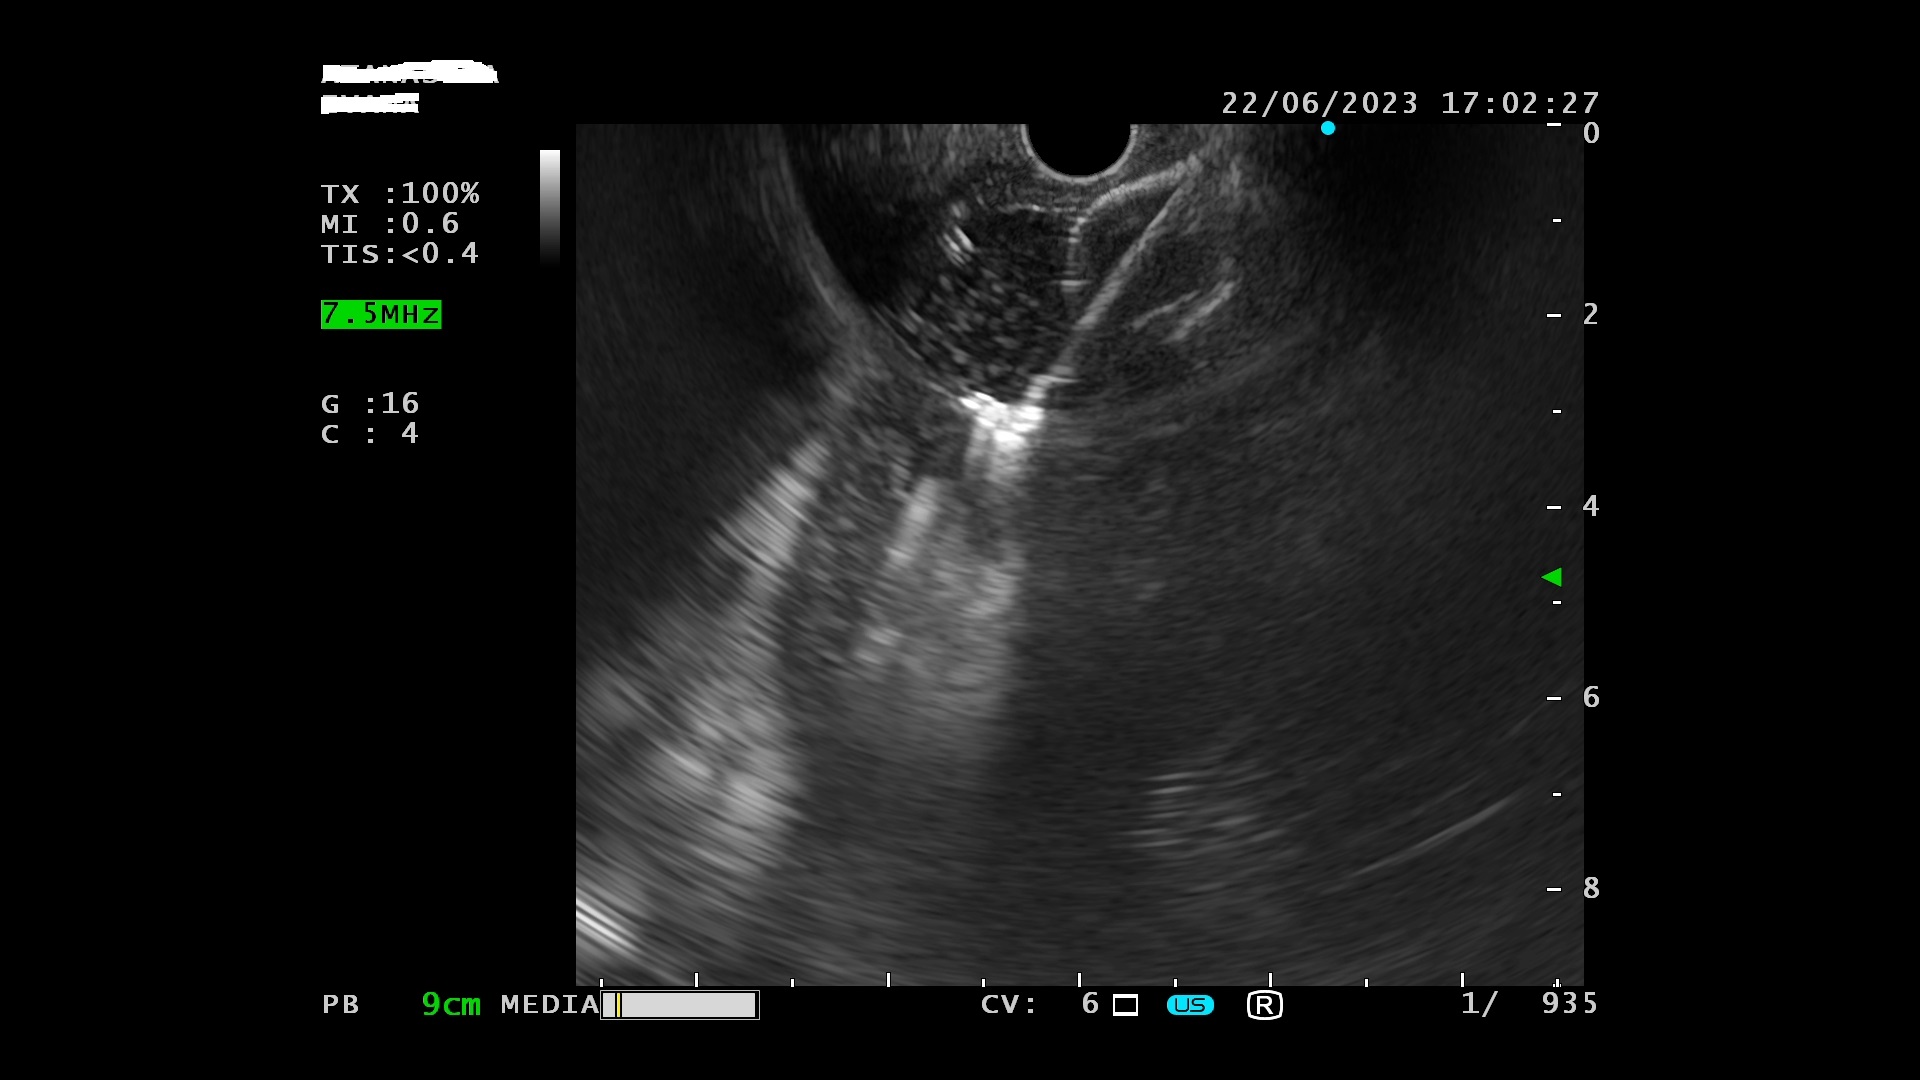

Ο ασθενής υποβλήθηκε σε ενδοσκοπικό υπέρηχο που έδειξε μια υποηχοϊκή μάζα διαμέτρου 21 χιλιοστών, με σαφή όρια, στην παγκρεατική κεφαλή και μεγάλη διάταση του χοληδόχου πόρου και του παγκρεατικού πόρου (διάμετρος 12 χιλιοστά).

Η μάζα είχε ξεκάθαρο διαχωριστικό όριο λίπους από την άνω μεσεντέριο φλέβα και δεν διηθούσε κανένα άλλο μεγάλο αγγείο της περιοχής (πυλαία φλέβα, σπληνοπυλαία συμβολή και αρτηρίες). Έγινε βιοψία με λεπτή βελόνη (FNA Χ3) και το κυτταρολογικό υλικό ήταν θετικό για αδενοκαρκίνωμα παγκρέατος. Το νεόπλασμα κρίθηκε χειρουργήσιμο και ο ασθενής υποβλήθηκε σε επέμβαση Whipple κατά την οποία αφαιρέθηκε πλήρως η παγκρεατική κεφαλή και ο όγκος σε υγιή όρια αλλά και 12 λεμφαδένες που ήταν όλοι αρνητικοί για κακοήθεια. Ο ασθενής υποβάλλεται σε συμπληρωματική χημειοθεραπεία.

Ενδοσκοπικός υπέρηχος: διάταση παγκρεατικού πόρου

Μάζα σώματος παγκρέατος στον ενδοσκοπικό υπέρηχο